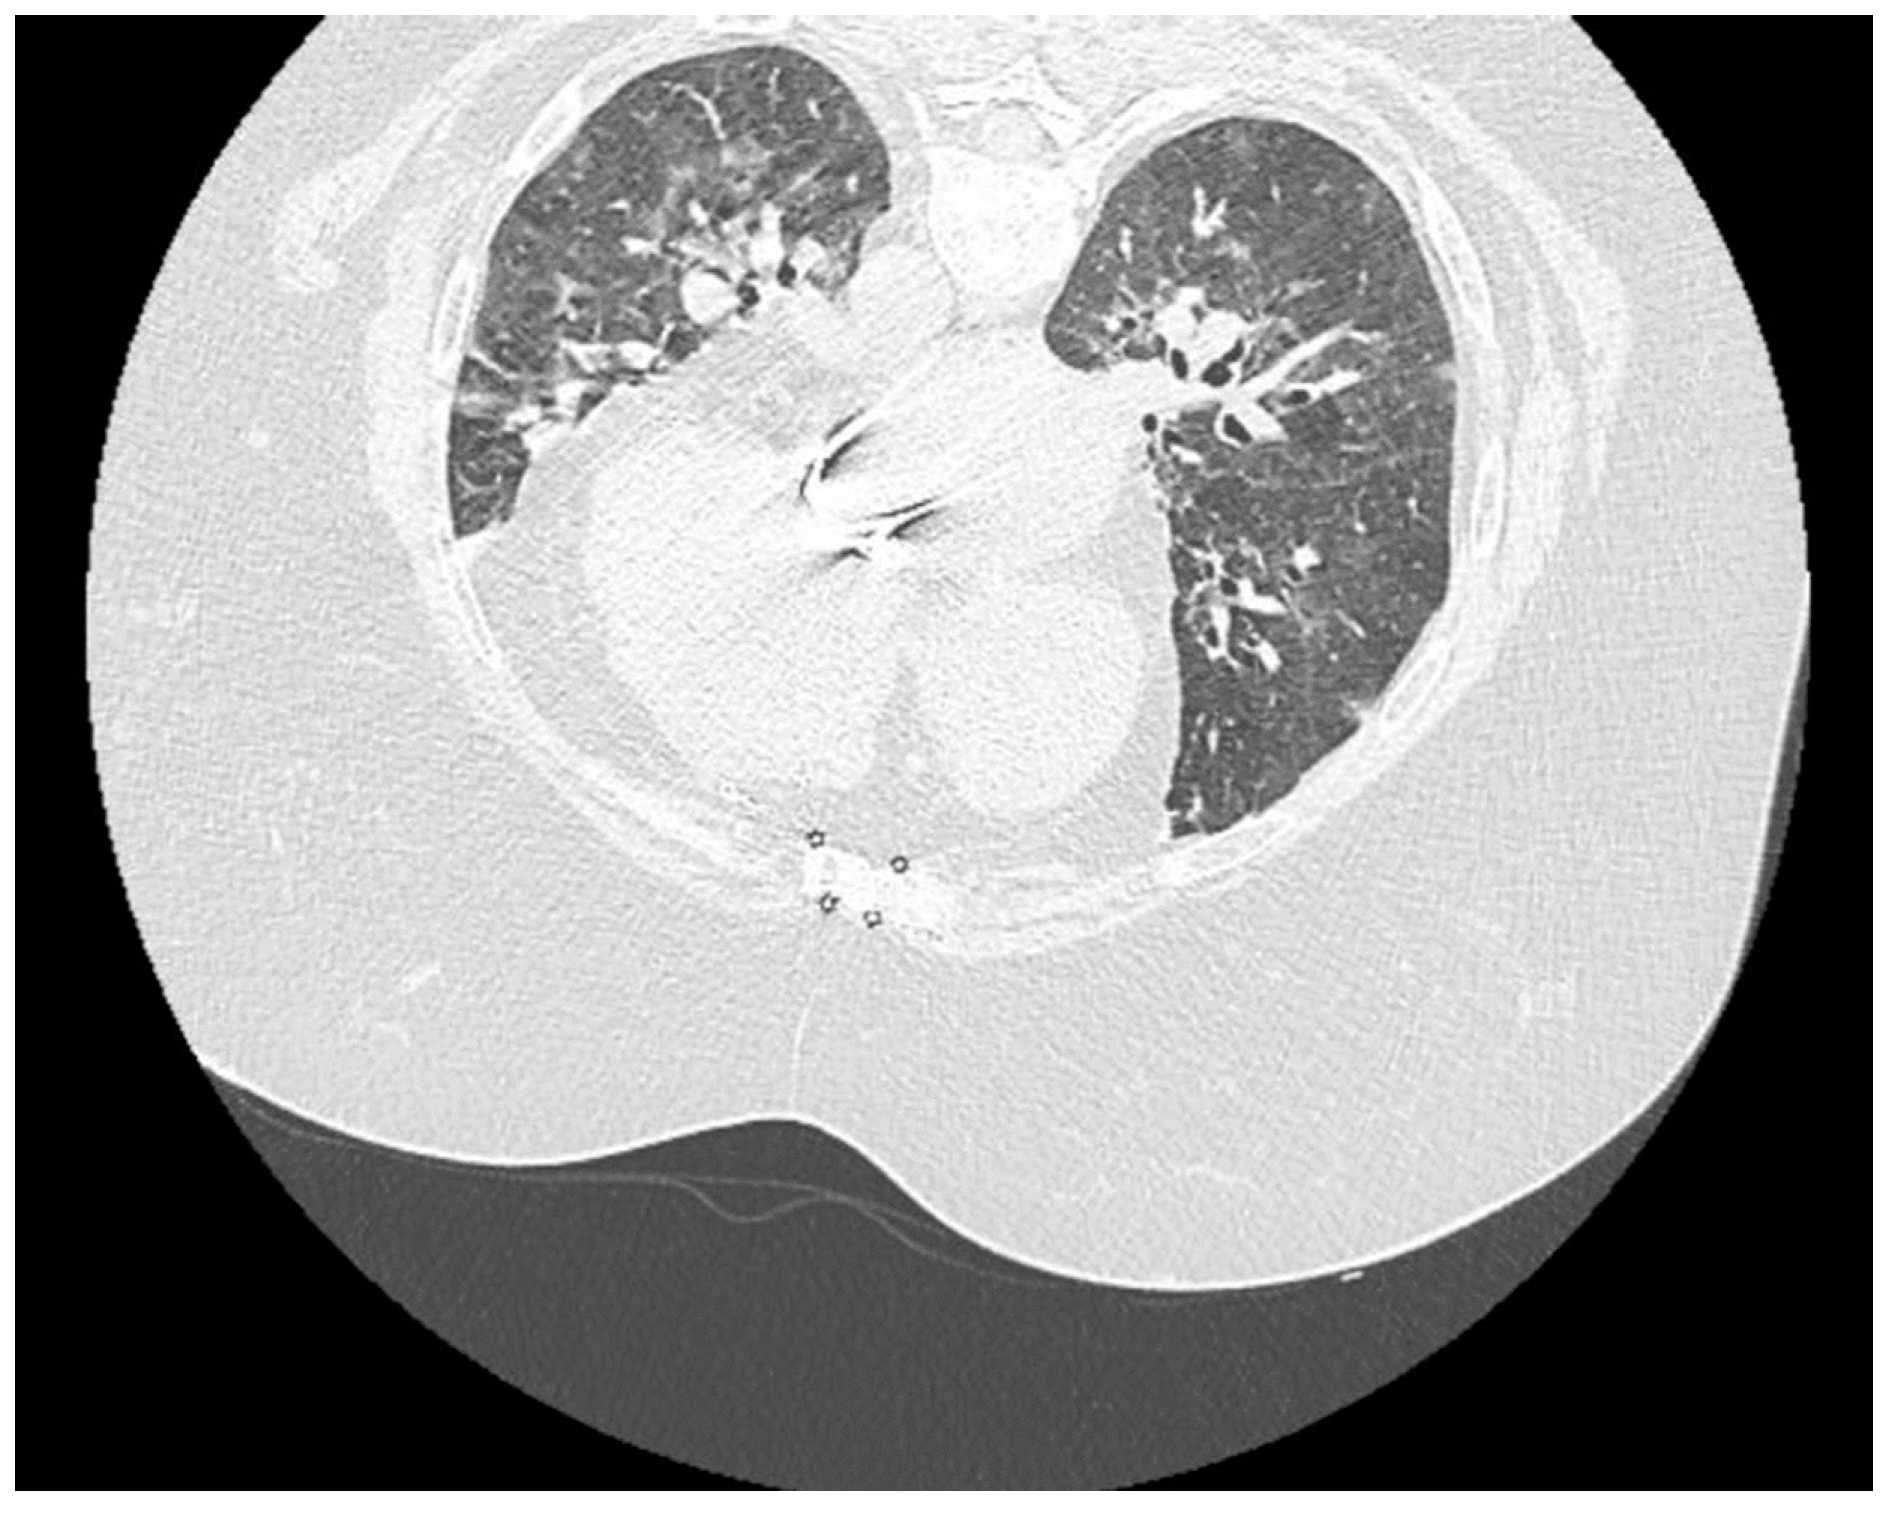

| Clinical signs and Imaging | Fever, headache, fatigue, dizziness Hemodynamic and respiratory stabile CT: ≈10% | Systemic Inflammatory Response Syndrome (SIRS) | Complementary paraclinical examinations | Nitrogen retention syndrome and SIRS decrease | CT ≈50-60% Severe form of SARS-CoV-2 pneumonia | ||||||